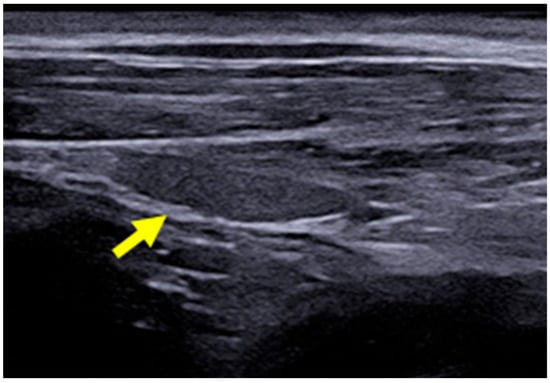

2.3. B-Mode Thyroid Ultrasonography

The B-mode ultrasound study of the thyroid was performed using the MyLabTM X8 Platform equipment (Esaote, Firenze, Italy), with a 4–15 MHz multi-frequency and linear transducer. The settings for gain, frequency, focus, time gain compensation (TGC), and depth were adjusted according to the physical characteristics of each dog participating in the study. The lobes of the thyroid gland were identified in their typical location, situated between the sternocephalic and sternothyroid muscles, ventral to the trachea and caudal to the larynx. Both were evaluated in a longitudinal manner with regard to their dimensions (length and width) and echogenicity in relation to the adjacent muscles (hypoechoic, isoechoic, or hyperechoic) and surface regularity. The aforementioned characteristics were also assessed in the transverse section, except for the dimensions (Figure 1). Figure 2 presents the right thyroid lobe on B-mode ultrasound in a longitudinal section of a female dog.

Figure 2. B-mode ultrasound images of the right thyroid lobe of a 3-year-old female dog (yellow arrow).